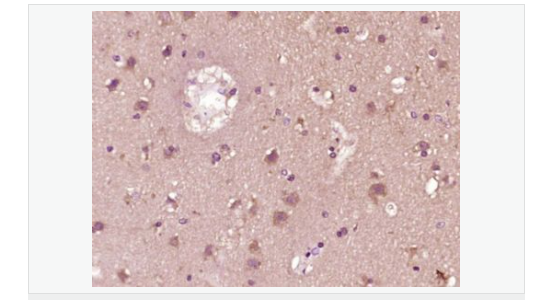

| 产品应用 | WB=1:500-2000 ELISA=1:5000-10000 IHC-P=1:100-500 Flow-Cyt=1ug/test (石蜡切片需做抗原修复) not yet tested in other applications. optimal dilutions/concentrations should be determined by the end user. |

| 产品介绍 | IRF7 encodes interferon regulatory factor 7, a member of the interferon regulatory transcription factor (IRF) family. IRF7 has been shown to play a role in the transcriptional activation of virus-inducible cellular genes, including interferon beta chain genes. Inducible expression of IRF7 is largely restricted to lymphoid tissue. Multiple IRF7 transcript variants have been identified, although the functional consequences of these have not yet been established. [provided by RefSeq, Jul 2008] Function: Transcriptional activator. Binds to the interferon-stimulated response element (ISRE) in IFN promoters and in the Q promoter (Qp) of EBV nuclear antigen 1 (EBNA1). Functions as a molecular switch for antiviral activity. Activated by phosphorylation in response to infection. Activation leads to nuclear retention, DNA binding, and derepression of transactivation ability. Subunit: Homodimer. Subcellular Location: Nucleus. Cytoplasm. The phosphorylated and active form accumulates selectively in the nucleus. Tissue Specificity: Expressed predominantly in spleen, thymus and peripheral blood leukocytes. Post-translational modifications: In response to a viral infection, phosphorylated on the C-terminal serine cluster. Phosphorylation, and subsequent activation is inhibited by vaccinia virus protein E3. TRAF6-mediated ubiquitination is required for IRF7 activation. Similarity: Belongs to the IRF family. Contains 1 IRF tryptophan pentad repeat DNA-binding domain. SWISS: Q92985 Gene ID: 3665 Database links: Entrez Gene: 3665 Human Entrez Gene: 54123 Mouse Omim: 605047 Human SwissProt: Q92985 Human SwissProt: P70434 Mouse Unigene: 166120 Human Unigene: 3233 Mouse Unigene: 101159 Rat Important Note: This product as supplied is intended for research use only, not for use in human, therapeutic or diagnostic applications. |